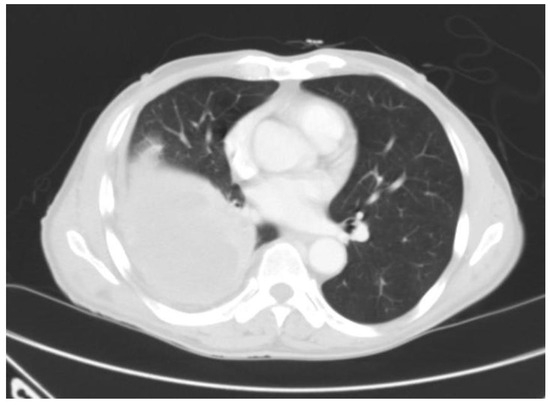

Tuberculous Empyema Presenting as a Persistent Chest Wall Mass: Case Report

by Jennifer Madeo, Rinal Patel, Wondwossen Gebre and Shadab Ahmed

Empyema necessitatis is an empyema that spreads outside of the pleural space involving the chest wall. Tuberculosis is the most common cause. It occurs in both immunocompetent and immunocompromised patients. Due to the long latency period and the paucity of symptoms, diagnosis can be challenging. Clinicians must have a high awareness of this disease, especially in patients from endemic regions. The disease is treatable with surgical and medical interventions. Failure to diagnose can lead to grave consequences for both the individual patient and public health. This is particularly true in endemic regions where controlling the spread of TB is challenging. We report a rare presentation of pulmonary tuberculosis in an otherwise healthy 72-year-old USA immigrant from Thailand. He presented with a painless, chronic chest wall swelling with minimal systemic symptoms. Imaging revealed empyema necessitatis. Histopathology could not give a definitive diagnosis because the tissue was too necrotic. Despite negative acid-fast staining, sputum cultures were positive for tuberculosis. The case presentation is followed by a brief review of the current relevant literature. This case highlights the importance of clinical suspicion and increased awareness for this silent but serious infection. Full article

Figure 1